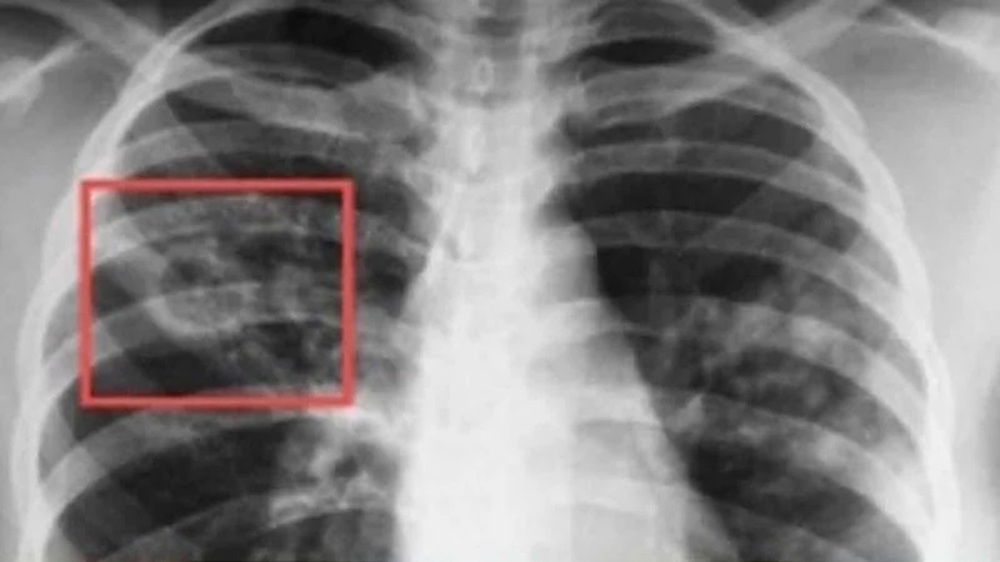

Безплатни прегледи за туберкулоза се организират в Пазарджик от 9 до 13 декември, съобщиха от Регионалната здравна инспекция.

Специализираната болница за активно лечение на пневмо-фтизиатрични заболявания (СБАЛПФЗ) "Д-р Никола Пенчев" обявява "Седмица на отворените врати“ Скрининговите прегледи за туберкулоза ще се провеждат 8:00 ч. до 12: 00 часа в лечебното заведение.

Кампанията се осъществява по Националната програма за превенция и контрол на туберкулозата в България за периода 2021 – 2025 г.

Данните на РЗИ показват, че през 2023 г. в област Пазарджик регистрирани 13 нови случая на туберкулоза, а заболеваемостта е 5,7 на 100 000 население. До края на юни т.г. заболелите са седем.